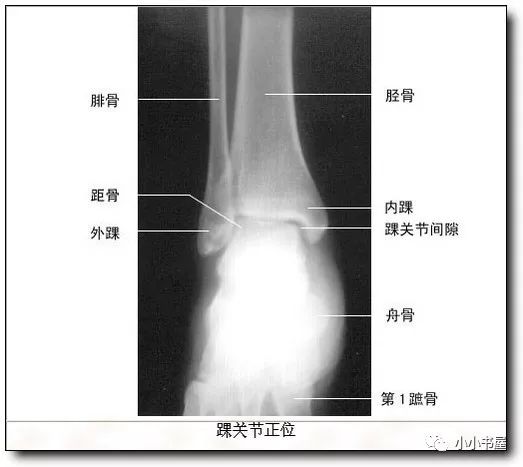

踝关节由三块骨组成,胫骨,腓骨和距骨,由胫,腓骨下端的下关节面,和

踝关节解剖1踝关节(anklejoint),由胫,腓骨下端的关节面与距骨滑车

踝关节解剖结构踝关节(ankle joint),由胫,腓骨下端的关节面与距骨

踝关节(ankle joint),由胫,腓骨下端的关节面与距骨滑车构成,故又名